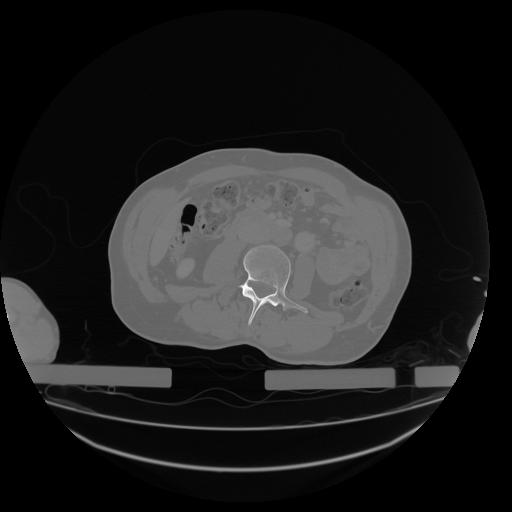

34 CUERPO,CE,Vol,1.0,CUERPO,,